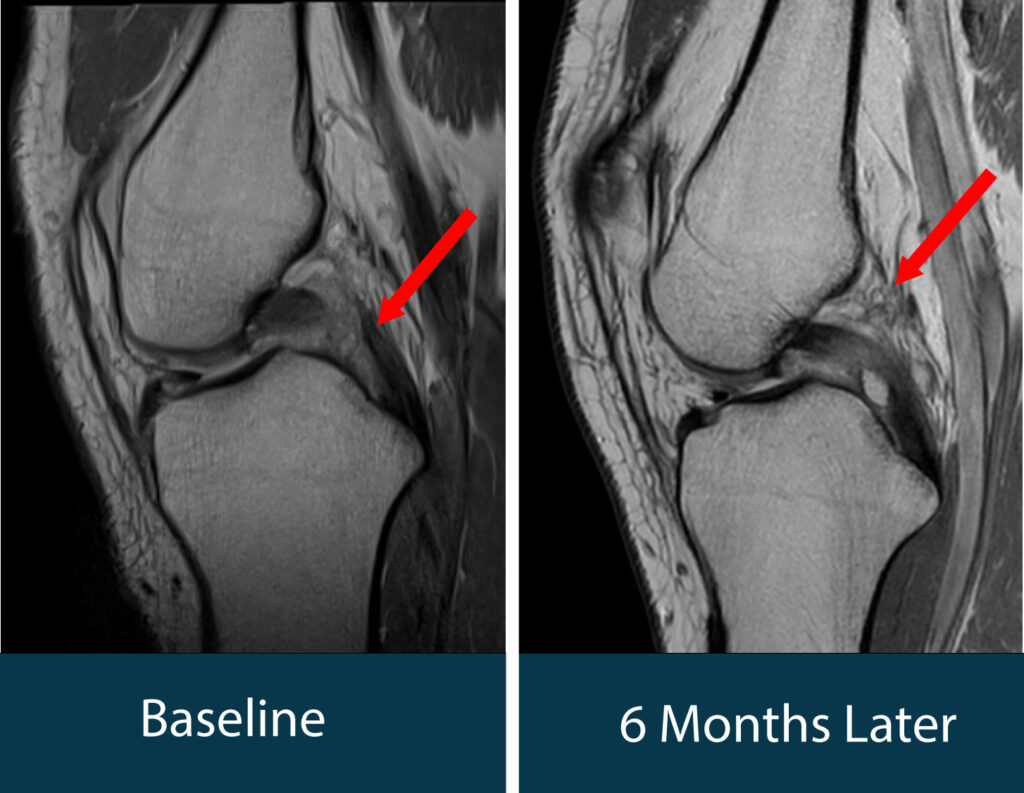

The rehabilitation lasted approximately six months. During this period, regular orthopedic evaluations and MRI scans were performed to monitor the healing process of the injured structures, including PCL stress tests. The course of treatment involved the typical ups and downs expected in an intensive rehabilitation program. Six months later, we were able to present an excellent outcome: MRI images confirmed complete healing of the posterior cruciate ligament.